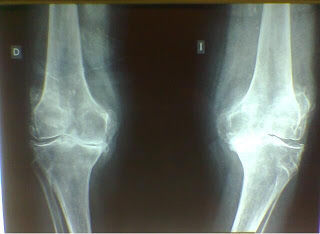

2. RX

1. - < EA

1. Osteofitos

1. Quistes subcondrales

1. > d. ósea subcondral= ESCLEROSIS SUBCONDRAL